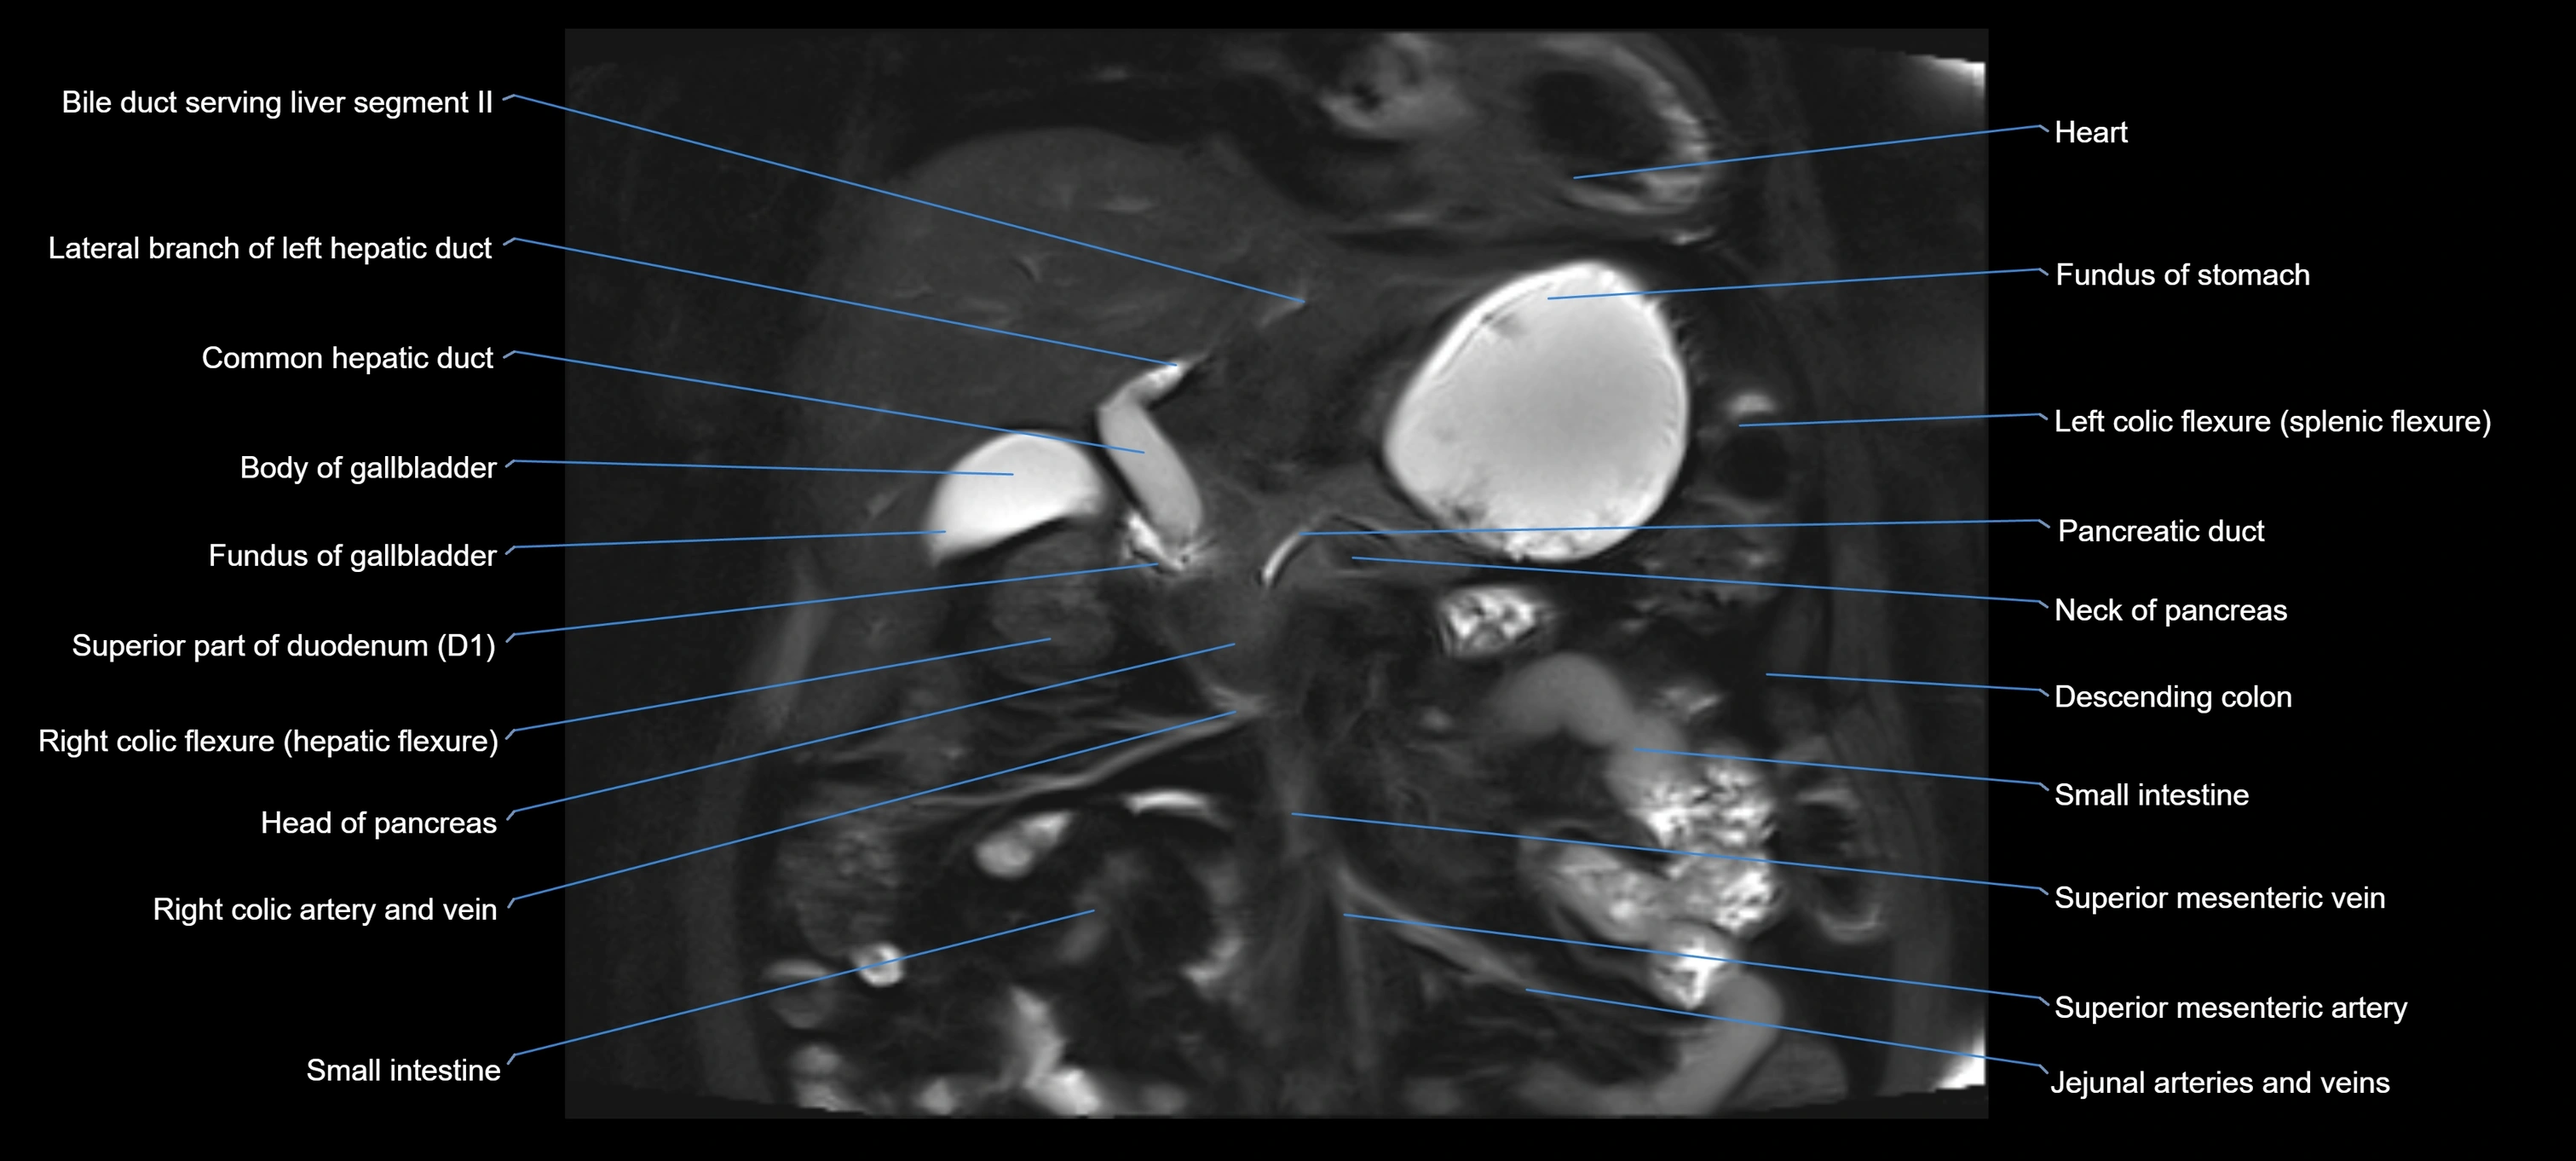

T2 TSE Fat-Saturated 3D (MRCP sequence):

• Duct visualized as a continuous bright tubular structure joining or parallel to the main pancreatic duct

• Allows 3D reconstruction of ductal anatomy and variants

• Excellent for diagnosis of pancreas divisum

Thick-slab T2 Fat-Saturated HASTE:

• Shows the accessory duct as part of the biliary–pancreatic system in a projectional image

• Highlights communication with main pancreatic duct and opening into the minor papilla

• Filling defects (stones, strictures) seen as dark spots within bright fluid

MRI image

image